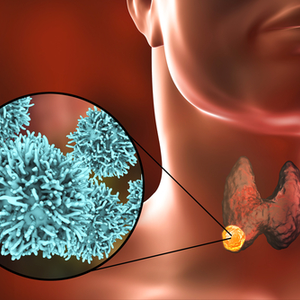

Vairogdziedzera vēzis